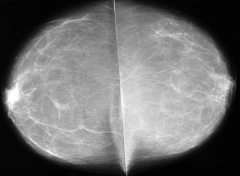

La mamografía se debe practicar en toda mujer a partir de los 40 años y dependiendo de los factores de riesgo debe continuar en controles anuales o bianuales hasta los 50 años a partir del cual debe continuar con examen mamográfico cada año.

DIAGNOSTICO

Se lleva a cabo a través de un proceso que inicia con lo que la paciente refiera de su autoexamen; la información es corroborada durante el examen médico que a su vez se apoyara en exámenes imagenologicos como mamografía o ecografía Según los hallazgos estará indicada la toma de una muestra de tejido mediante una biopsia.